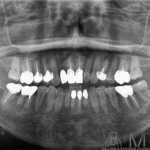

術前パノラマ画像所見

7-3 1┴1-7は残存歯、2┘は欠損。6541┴146は失活歯。5┴46はper様所見を認める。上顎は中等度~高度の水平性骨吸収を認める。7┴7で強い。両側上顎骨の異常吸収像を認める。 下顎は7-1┬1-7は残存歯。761┬126は失活歯。明らかな根尖病変を示唆する歯は認めない。軽度~中等度の水平性骨吸収を認める。